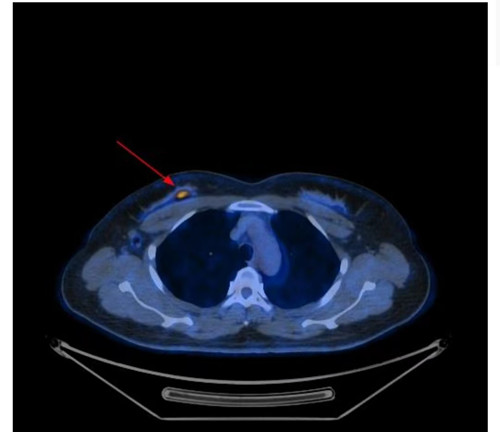

PETCT显示右侧乳腺内糖代谢明显增高的结节和腰椎的转移癌

问题来了,彭女士腰椎转移癌原发灶在哪里?是甲状腺癌吗?因关系后续治疗方案,在医生的建议下,彭女士到湖南省人民医院PET影像中心进行PET/CT扫描。检查结果让人大吃一惊,彭女士的右侧乳腺有一个糖代谢明显增高的结节,大小为10mm,高度提示右侧乳腺癌。这下解开了腰椎转移癌的谜底,乳腺癌除腰椎骨转移外,同时发现右侧腋窝淋巴结和骨盆多骨的转移。目前,彭女士已经转入乳甲外科接受手术及进一步治疗。